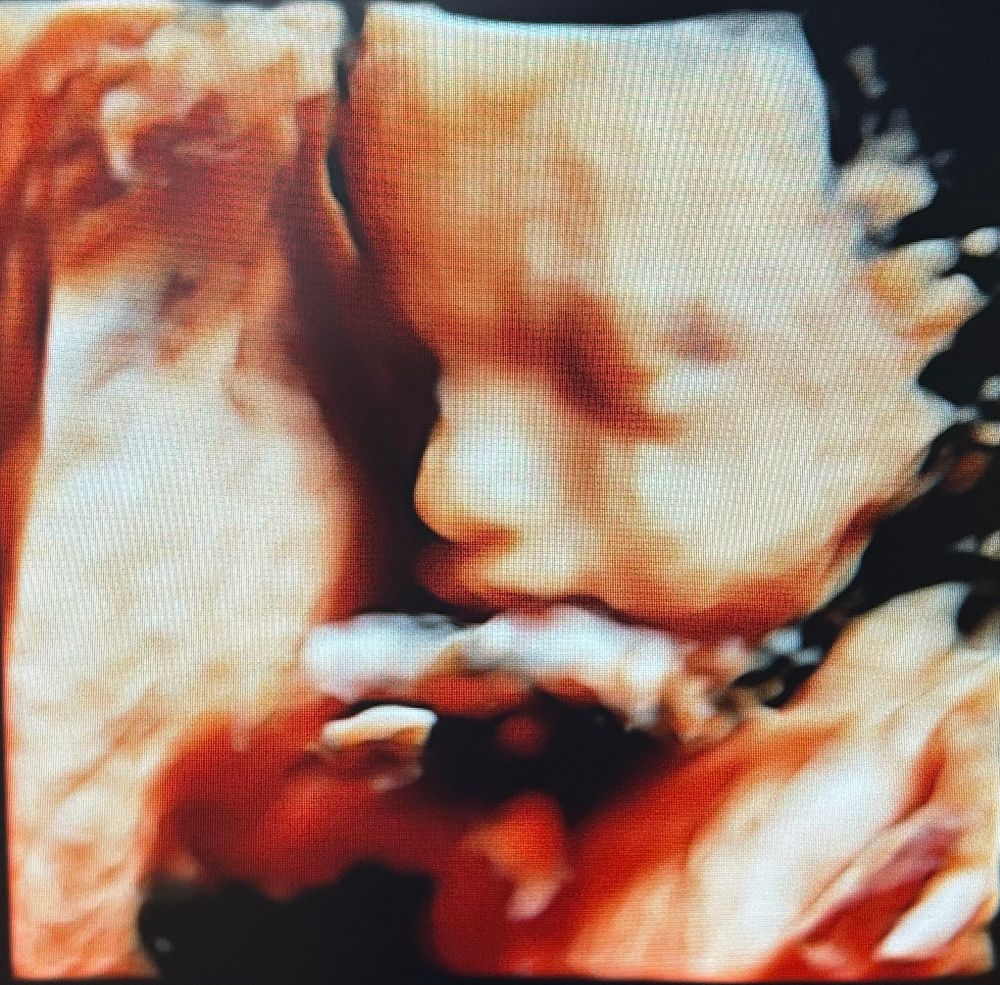

3D узи Калуга

Узи 7 недель, отставание по ктр или ошибка узи? Очень нужна поддержка Ктг, узи, доплер